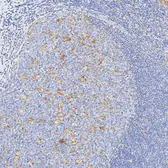

Description Rabbit MonoclonalApplications IHC-PReactivity HuSummary Highly recommended for IHC-P in human tissues. Autostainer protocol information available.